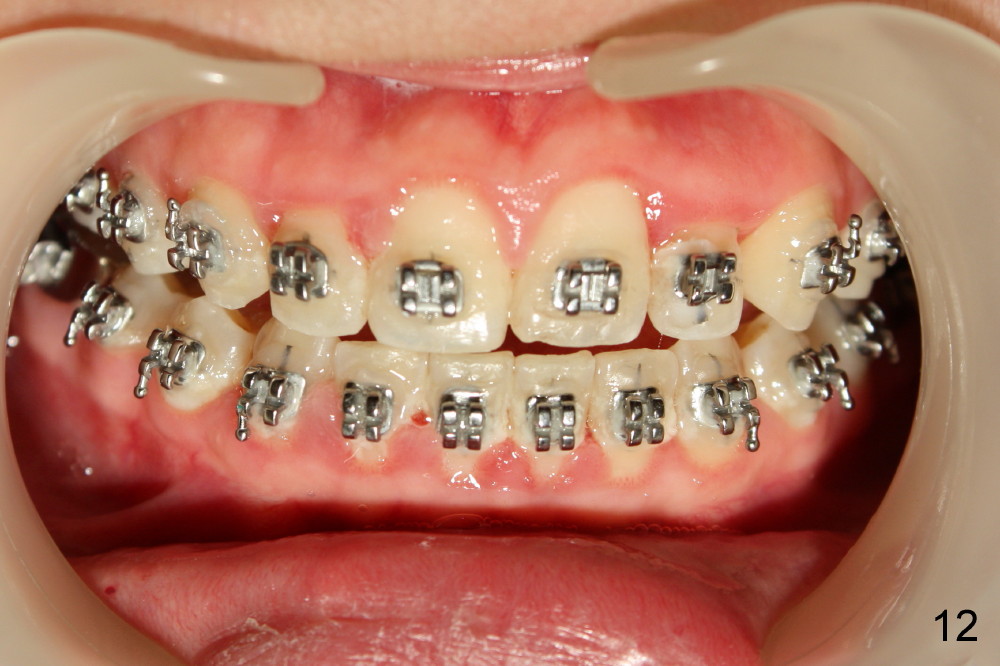

Another one month later, UL2 is moved labially and a bracket is placed (upside down in order to fix torque problem associated with cross bite correction). Surprisingly, it works perfectly: UL2 orientation is right (Fig.12,13,14). The distal diastema (Fig.14 <) is to be closed by power chain. The palatal expander is removed since the posterior cross bite has been a little overcorrected (Fig.14,15, as compared to Fig.1,2,4-7).